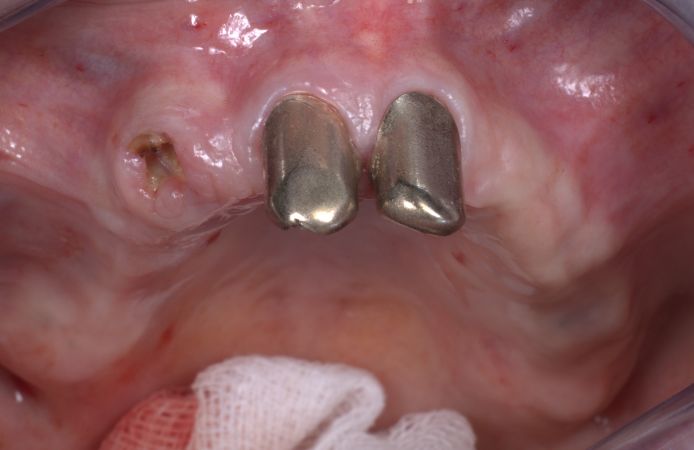

Figure 10.

The angulated Neoss Multi-Unit Abutments re-aligned the prosthesis interfaces to achieve a passive fit of the prosthesis.